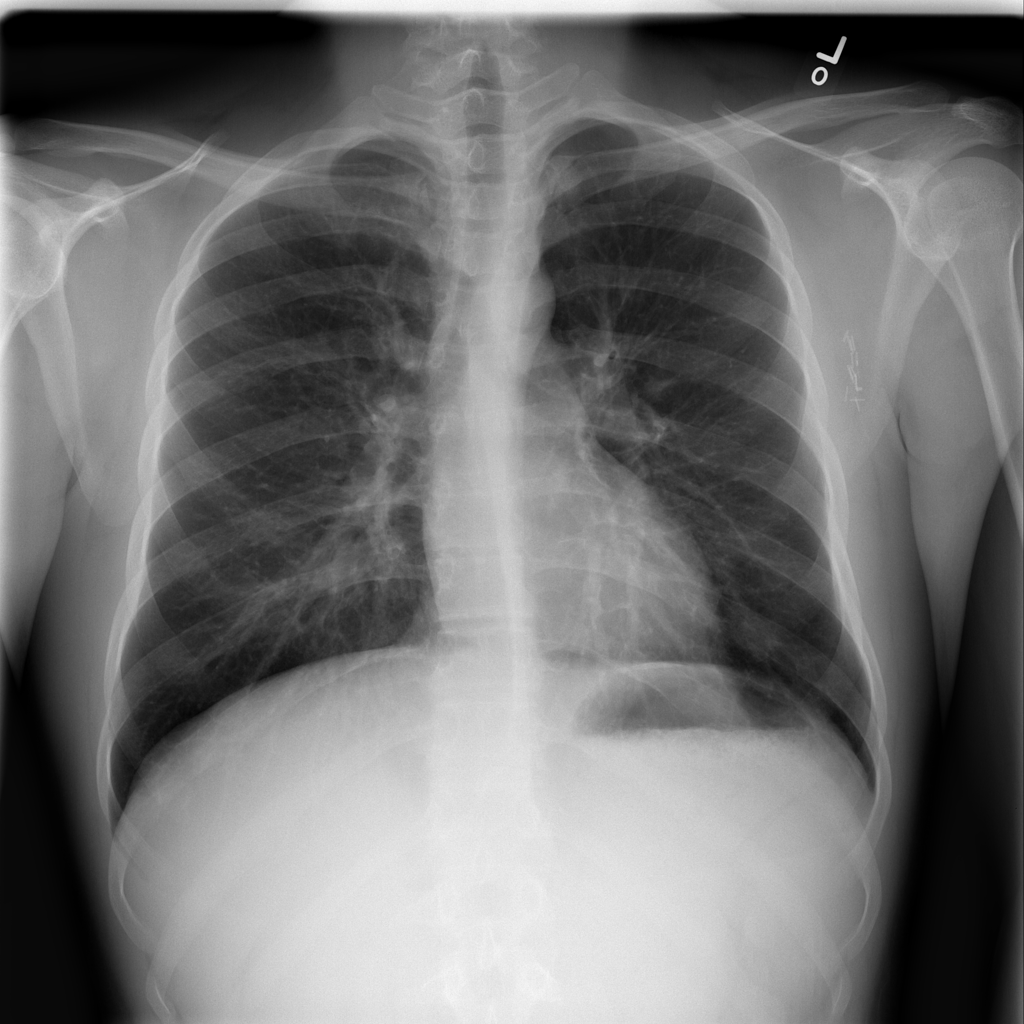

Showing up to 90 reference images for Pneumonia.

PAT-C0E5 · IMG-015Pneumonia

PAT-C0E5 · IMG-015

AP